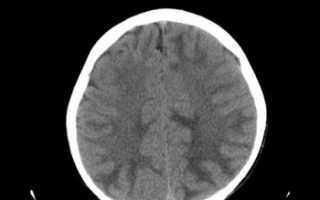

При подозрении на энцефалопатию применяются различные инструментальные методы диагностики. Рентгеновские лучи или магнитное поле помогают обнаружить объемные образования, мешающие нормальному кровообращению в сосудах головного мозга. Электроэнцефалография фиксирует электрическую активность мозга; её снижение указывает на нарушения в функциональном состоянии центральной нервной системы.